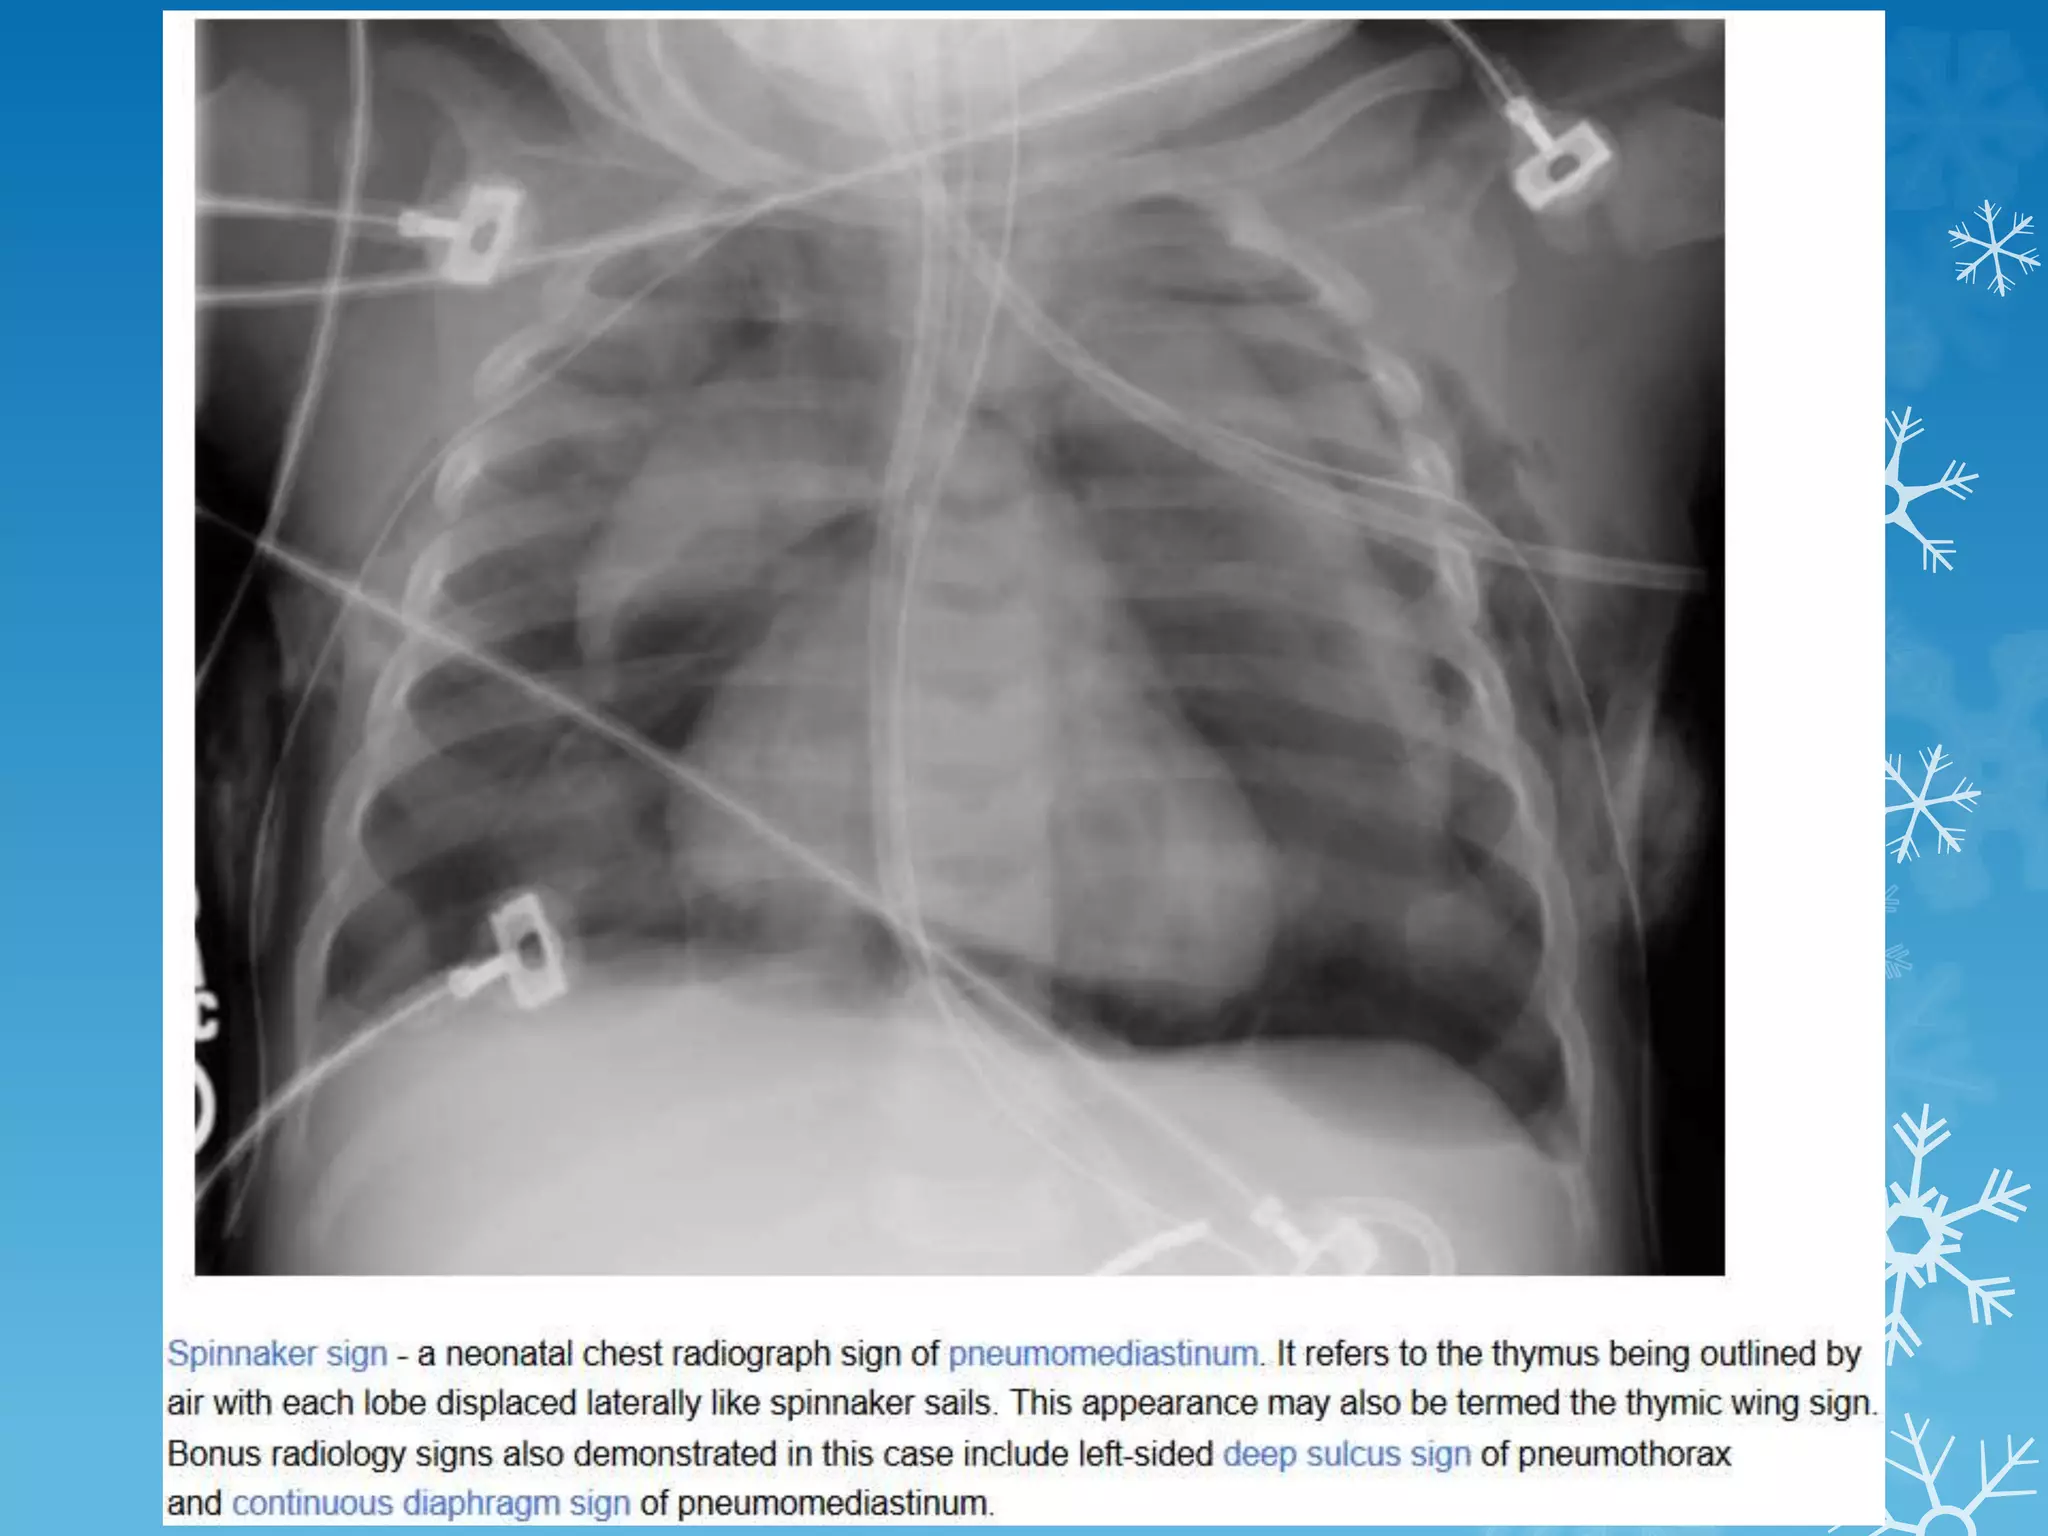

NAME THE SIGN & DIAGNOSIS

Corkscrew sign - midgut volvulus

Holly leaf sign - Asbestosis